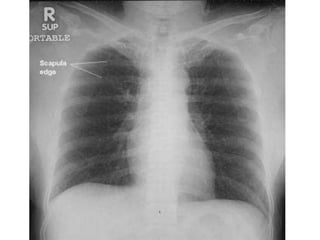

CXR